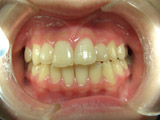

3番目の写真はH20 11月です ほとんどずれなく並ぶことが出来ました。

取り外し式の装置なので、ワイヤーは使っていません。

本人や両親の方と話し合いこれで経過観察となりました。

おおよそ1年半の治療で9万円で出来ました。